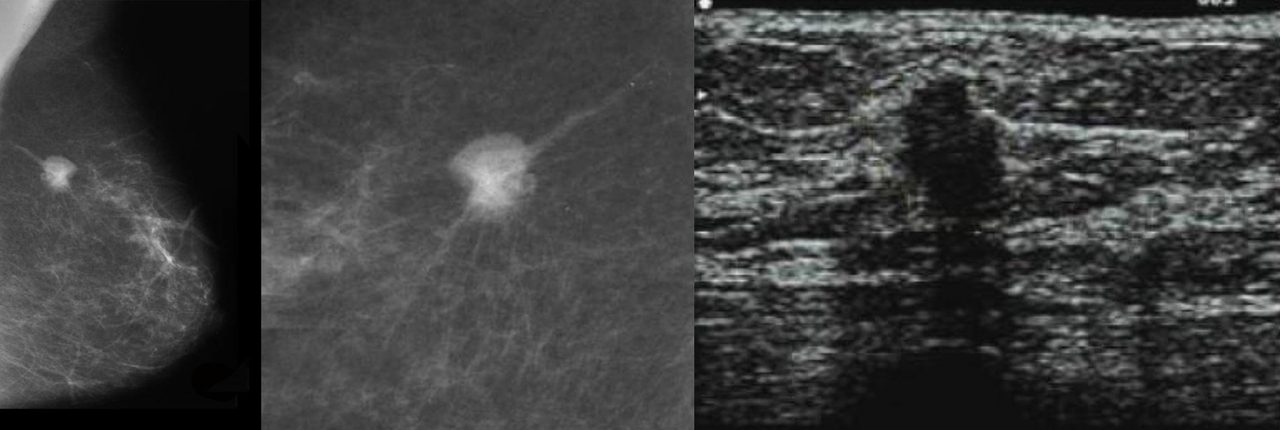

Voici les clichés des examens que Mme V. a réalisés selon votre prescription.

Question 4 – À propos de ces examens, il vous semble que (une ou plusieurs réponses exactes) :

On observe un nodule de contenu solide (non liquidien).

Le radiologue décrit une lésion tissulaire du quadrant supéro-externe solide de 28 mm de diamètre, classée ACR 5.